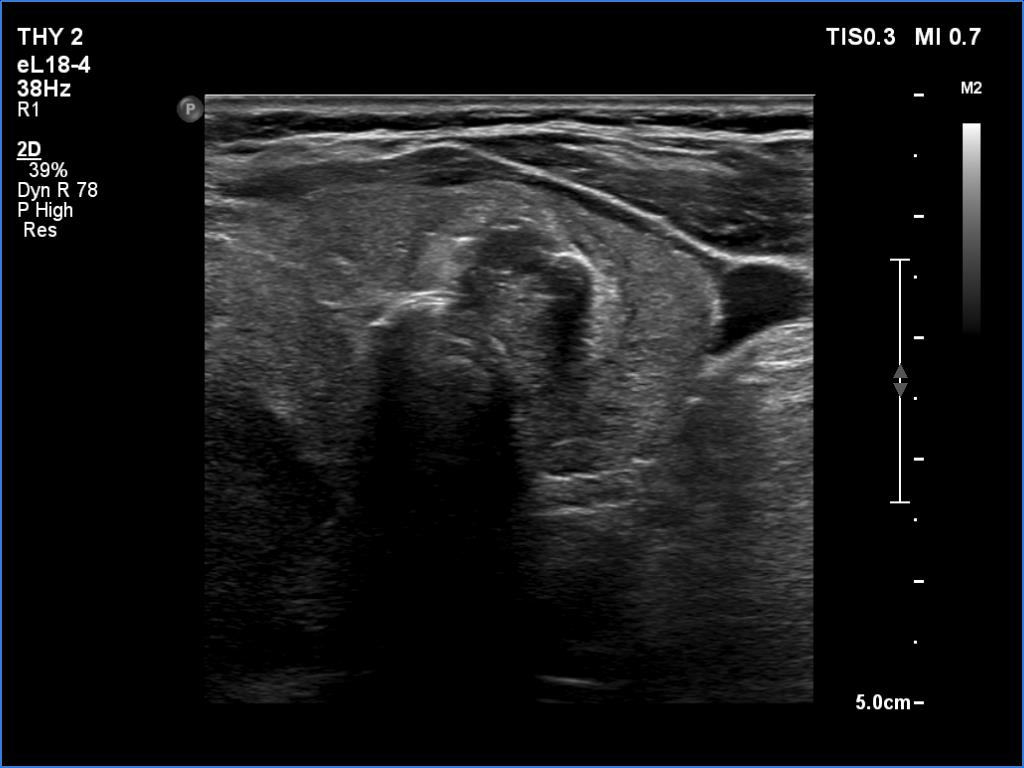

Ultrasonography. There was an irregular, large hypoechoic mass in the right lobe. The nodule has irregular, lobulated margins and was hard on elastography. A much smaller, similar nodule was in the lower-medial part of the left lobe.